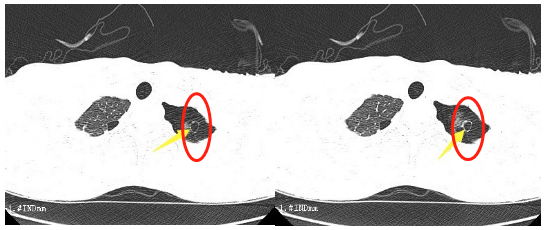

这段时间,16岁的小王突然出现了胸闷的症状,持续一周都不见好转。到我院胸心外科检查后,胸片提示左侧液气胸,积气为主,结合患者术前CT检查情况,考虑为肺大泡破裂引起的气胸。

“肺大泡,也叫肺大疱,是指由于各种原因导致肺泡腔内压力升高,肺泡壁破裂,互相融合,在肺组织形成的含气囊腔。”胸心外科医生邓意平说,肺大泡的增大或增多,会使肺功能发生障碍并逐渐出现症状,像小王这样年纪轻轻的小伙子也可能出现胸闷、气短等症状。

患者肺大泡明显,术后切口较小。